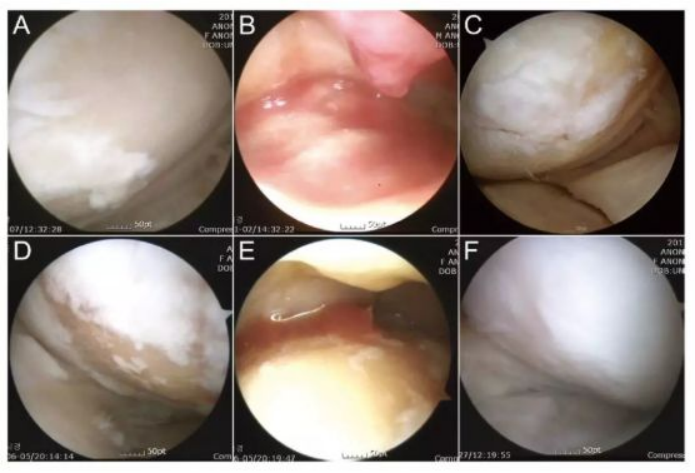

下图a为治疗前关节镜检查结果,可以看出软骨存在缺损。图b为脂肪间充质干细胞联合PRP治疗,图c为治疗后结果,通过间充质干细胞治疗,软骨得到了修复。

下图中A-C为51岁男性膝关节镜,D-F为54岁女性膝关节镜。A/D为治疗前,白色示意软骨,浅黄色示意裸露的骨。B/E为间充质干细胞注射。C/F为治疗后的关节镜检查。